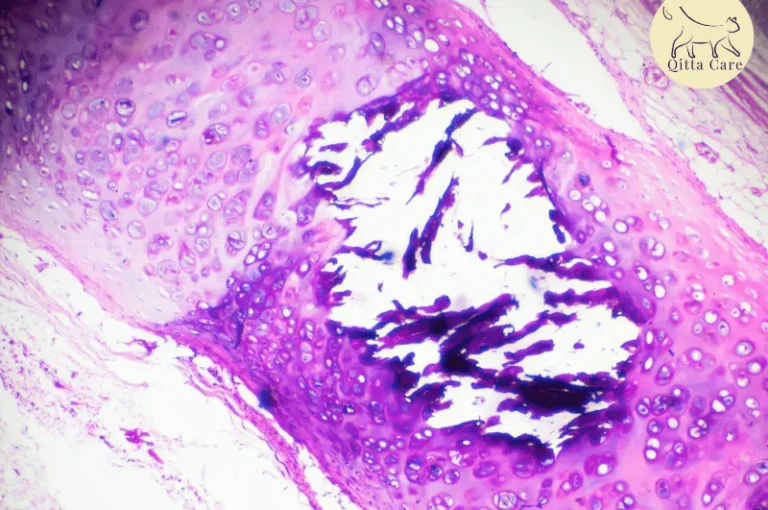

طرق علاج خراج القطط

إذا كنت من مربي القطط، فمن المحتمل أنك سمعت عن مشكلة “خراج القطط”. ولكن هل تعلم أن هذا المرض أكثر من مجرد عدوى بسيطة؟ الخراج هو تجمع موضعي للقيح يتشكل داخل الجسم نتيجة للعدوى البكتيرية أو الصدمات الجسدية. المشكلة قد ...